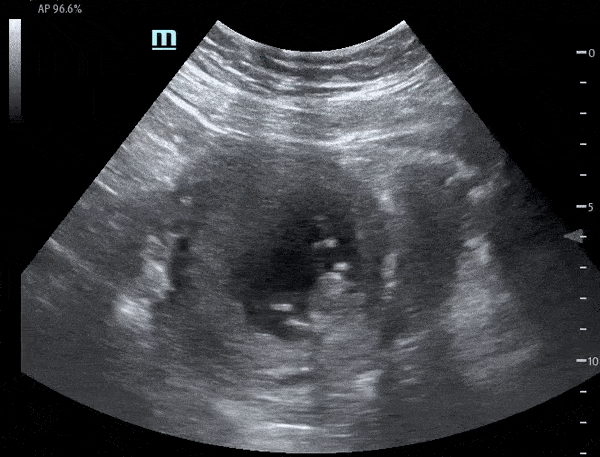

This is a sagittal view demonstrating a late first trimester pregnancy with fetal movement and cardiac motion. Michael Macias